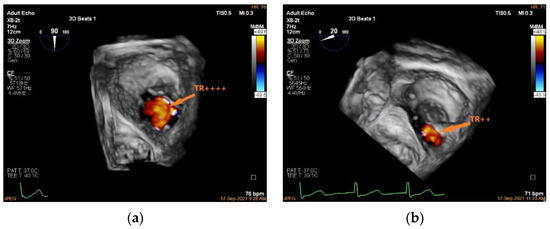

3.5. Valve Function Assessment